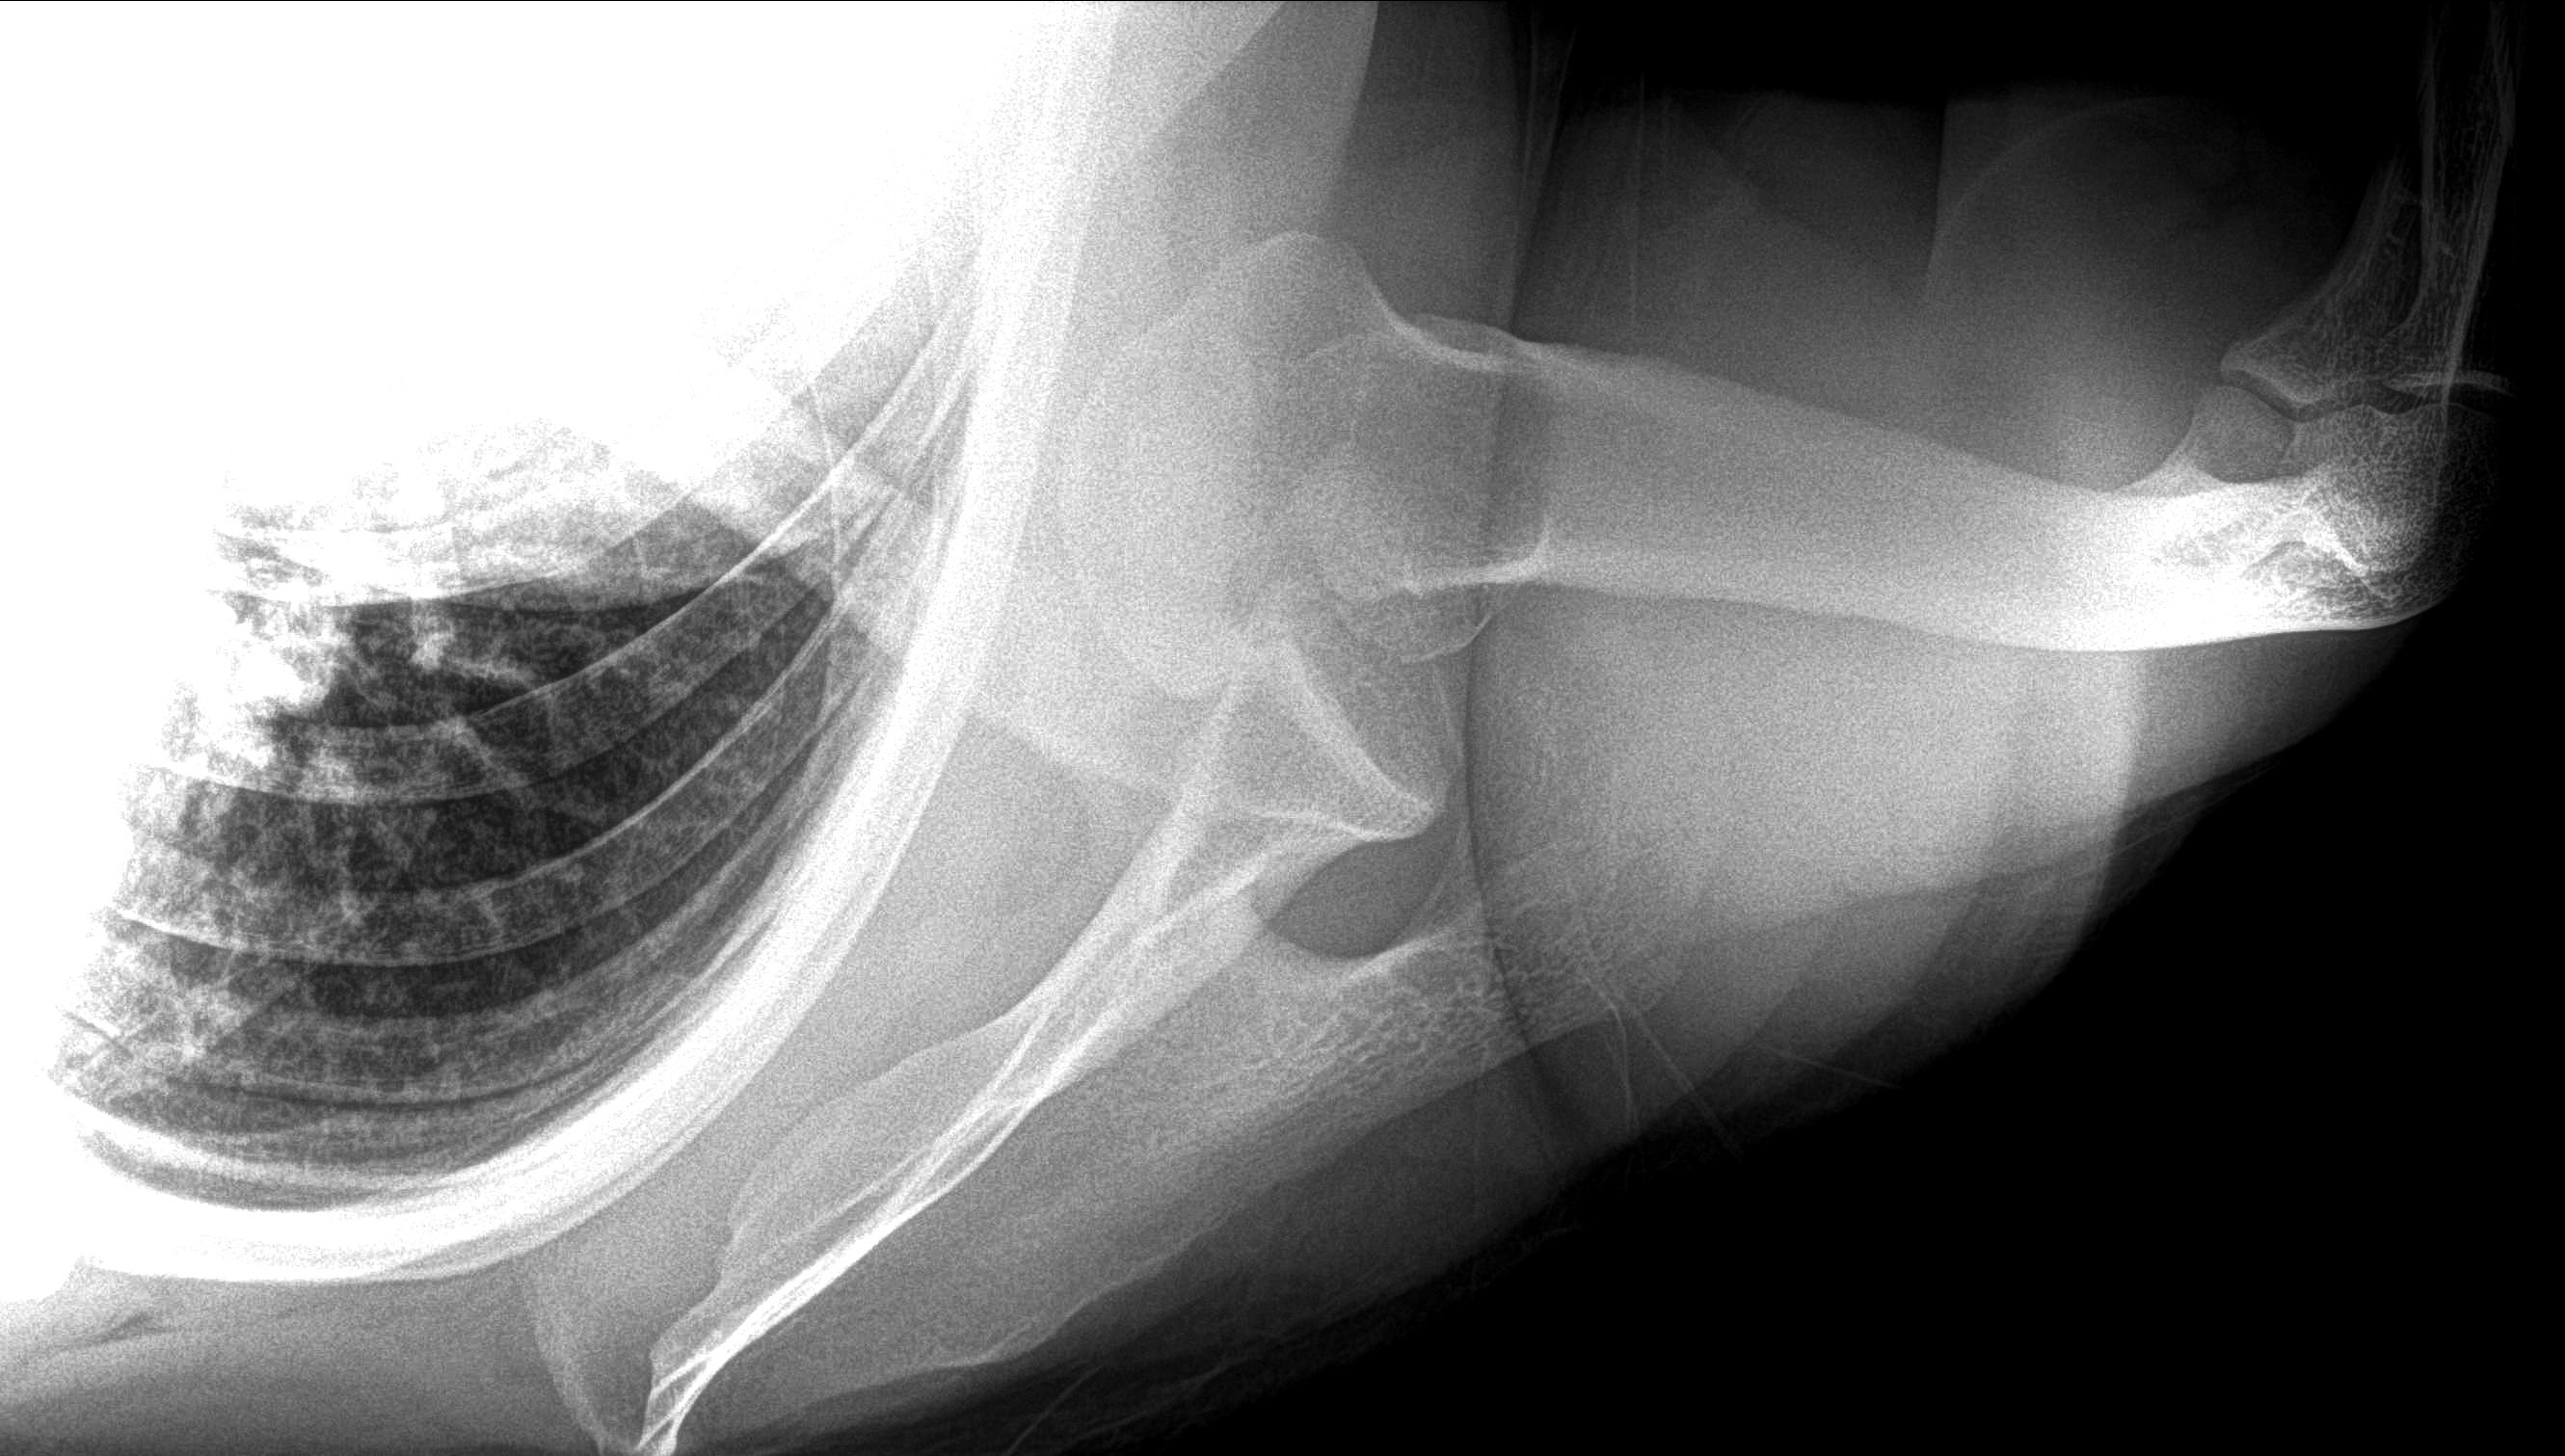

Shoulder Dislocation With Multiple Fractures

An X-ray showing a dislocation of the shoulder that also contains multiple fractures.